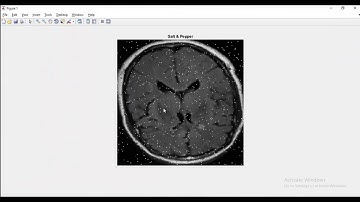

Classification of MRI images for Alzheimer disease detection in Matlab